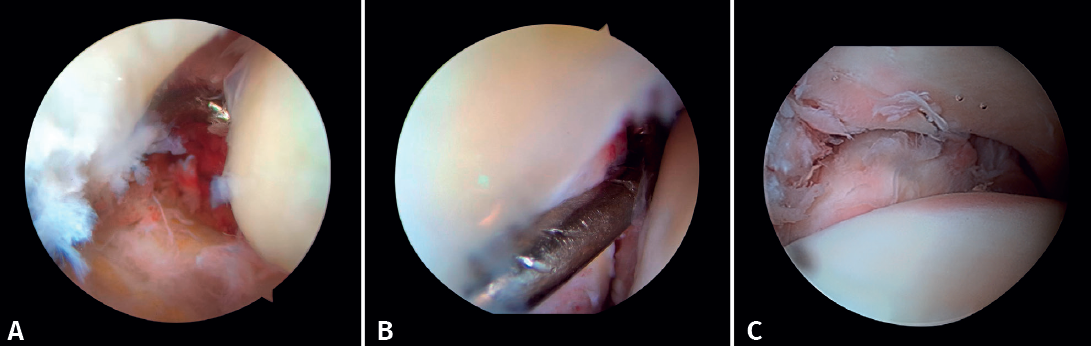

- Diagnosis of syndesmotic instability. Arthroscopy allows assessment of the integrity of the syndesmosis and the MCS on the radiograph and CT scan, especially in SER II and IV fractures. It has been shown that radiographic assessment is not always predictive of the syndesmotic lesion. In addition, arthroscopy ensures its anatomical reduction. Takao found that 87% (33/38) of the ankles with fractures had syndesmosis lesions detected by arthroscopy(20).

Arthroscopy allows both direct visualization and dynamic assessment of the syndesmosis(21,22).

- It makes it possible to differentiate between SER II fractures (where there should be no syndesmosis damage) and SER IV fractures, where the syndesmosis is affected and can be stabilized(5,23).

- Arthroscopy can avoid the false impression of a widened medial joint space on fluoroscopy due to congenital anomalies.

- Being able to visualize the malleolar incisura together with radioscopic control allows us to ensure correct positioning of the incisura fibularis, especially in patients with unstable injuries where there is a risk of malreduction due to shortening or rotation of the fibula(5,24).

- Arthroscopy can help avoid overcorrection of the syndesmosis, which is highly arthrogenic(5,24) (Figure 6).

Figure 6. A: syndesmosis injury; B: control of reduction to avoid overcorrection; C: intraoperative control of correct reduction of the fibula at the incisura.